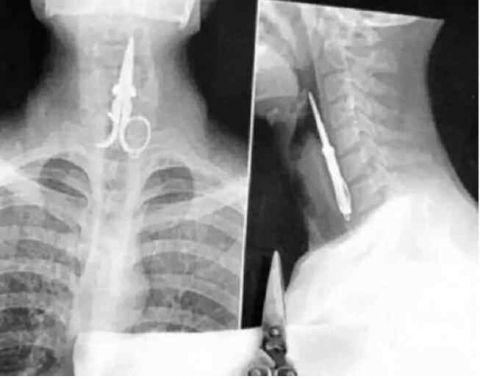

有时候大夫也会留下点什么东西在里面